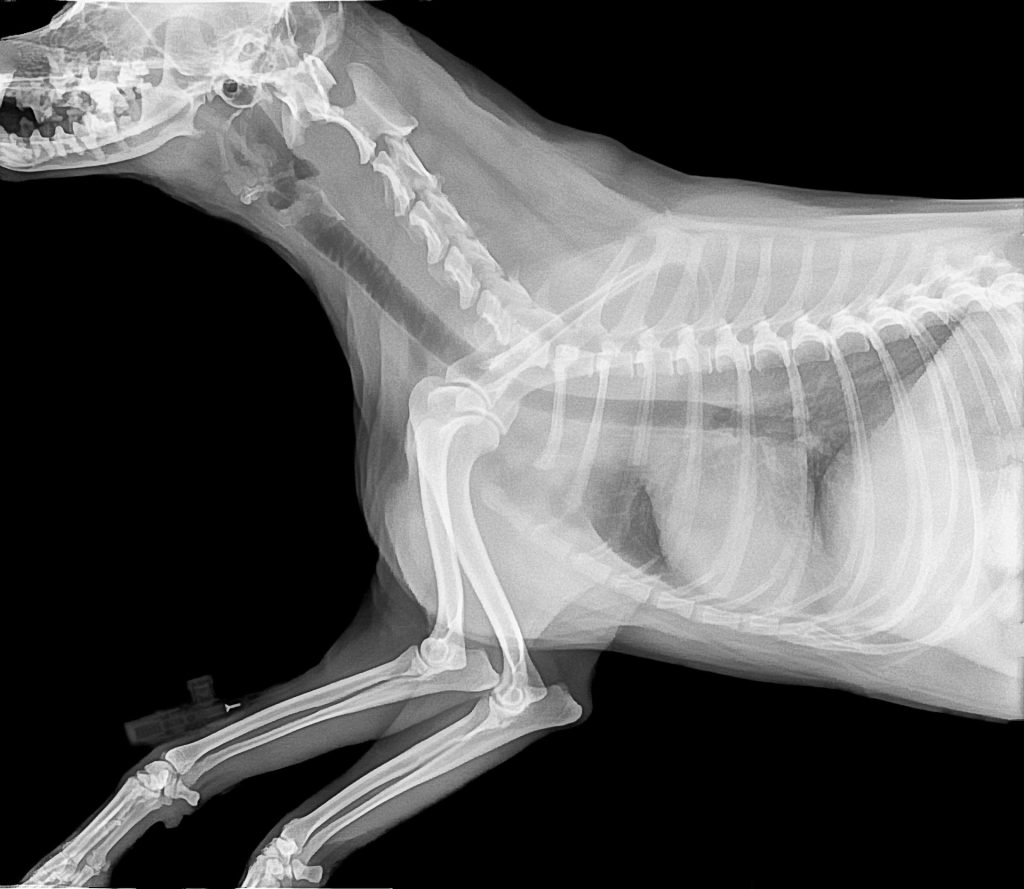

Digital Diagnostic Radiology

Our Blackburn vet uses X-rays to check or diagnose numerous cardiac, pulmonary, abdominal and musculoskeletal conditions. Our images are thoroughly reviewed so that we can figure out the next steps.